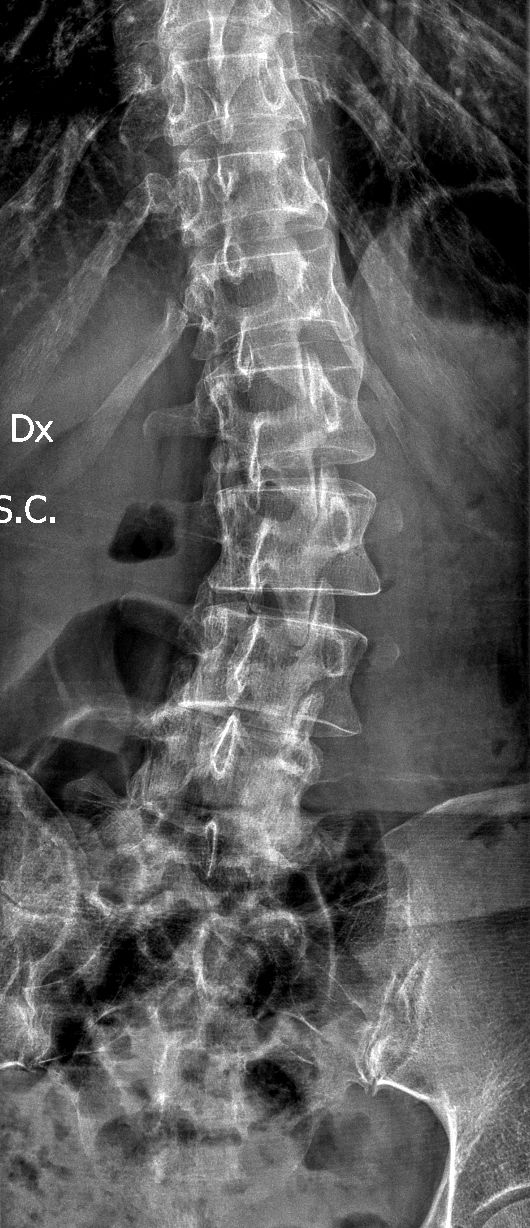

Dopo la laurea e la specializzazione in Neurochirurgia con lode presso il Policlinico Agostino Gemelli, ho dedicato la mia formazione esclusivamente alla cura delle malattie della colonna vertebrale e del midollo spinale, come ernie del disco, stenosi del canale vertebrale, spondilolistesi, metastasi vertebrali e tumori del midollo spinale, attraverso esperienze presso centri di riferimento italiani ed internazionali e a numerosi corsi e master di II livello.

Queste patologie si manifestano con sintomi neurologici (ad esempio: dolore o perdita di forza ad un arto, formicolii, rigidità o perdita di coordinazione alle mani o durante la marcia) oppure con sintomi meccanici (ad esempio: mal di schiena prevalente durante il movimento). Una valutazione specialistica deve mirare a correlare i sintomi clinici con le alterazioni presenti alle immagini radiologiche, ed a guidare il paziente attraverso il percorso di cura, finalizzato al recupero della sua ottimale qualità di vita.

• scoliosi degenerativa dell’adulto;

• cifosi degenerativa dell'adulto;

• deformità degenerative dell'adulto.